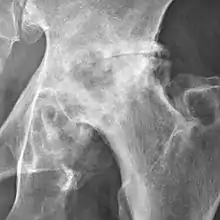

Osteoarthritis of the hip joint may also be graded by Tönnis classification. There is no consensus whether it is more or less reliable than the Kellgren-Lawrence system.[8]

_osteoarthritis_of_the_hip.jpg.webp)

| Grade | Description |

|---|---|

| 0 | No osteoarthritis signs |

| 1 | Mild:

|

| 2 | Moderate:

| 3 | Severe: